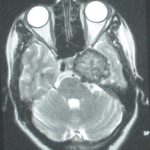

Cette masse peut entrainer notamment :

- Une irritation du cerveau qui se manifeste par une épilepsie

- Une compression voire destruction d’une partie du cerveau causant un affaiblissement ou une perte d’une fonction du cerveau

- Une augmentation de la pression à l’intérieur du crâne (espace inextensible à l’intérieur duquel vient s’ajouter le volume de la tumeur), ce qui va se manifester initialement par des maux de tête d’aggravation progressive qui vont s’associer à des nausées, des vomissements, des troubles visuels… Cet état peut aboutir à la perte de la vue dans les formes d’évolution lente et au décès dans les formes d’évolution rapide.